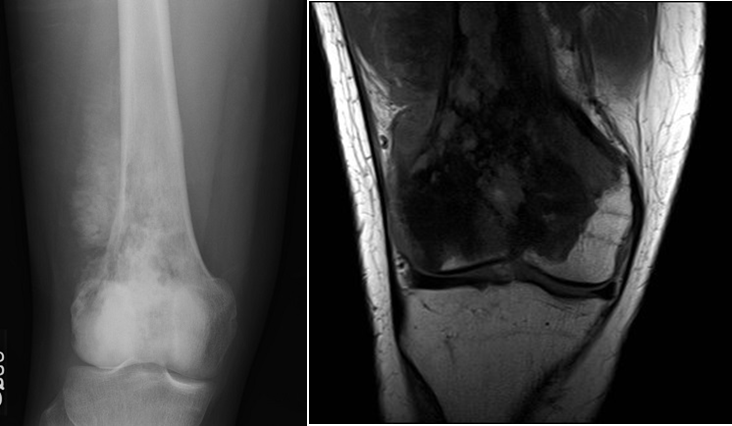

A 79-year old female presents with complaints of right hip pain for 2 months. She denies prior injury or precipitating event. The pain is made worse by lying on the affected side and occasionally hurts with hip motion. The pain is improved with NSAIDS and placing ice on the lateral aspect of her hip. Her primary care physician ordered x-rays which showed a bone lesion in the proximal femur. Her PCP was concerned she had bone cancer and ordered an MRI of the thigh to further evaluate. AP x-ray and a coronal MRI image are shown above. The patient denies a history of weight loss, fatigue, and history of cancer. On exam the patient has no pain with passive range of motion of the hip in all planes. She has pain with palpation over the greater trochanteric bursae. Motor and sensation are intact throughout the lower extremities. What is the most likely cause of this patient’s pain?